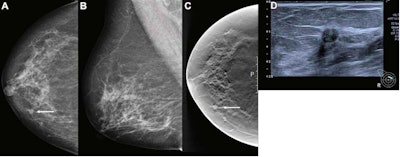

Hofvind et al wanted to compare the performance of a commercially available AI system (Transpara version 1.7.0, ScreenPoint Medical) with consensus, independent double reading in a population-based screening program. They also looked at the histopathologic characteristics of tumors with different AI scores ranging from 1 to 10.

A total of 957 breast cancers were included in the study, 752 being screen-detected and 205 being interval cancers. These came from 122,969 screening examinations taken between 2009 and 2018 from 47,877 women in Norway.

The team found that the AI system gave a score of 10 to 745 breast cancers out of the total (77.9%). That score applied to 653 of the screen-detected cancers (86.8%) and 92 of the interval cancers (44.9%) with threshold one.

Meanwhile 602 of the total screen-detected cancers (80.1%) and 63 of the interval cancers (30.7%) were selected by the system when threshold three was used.